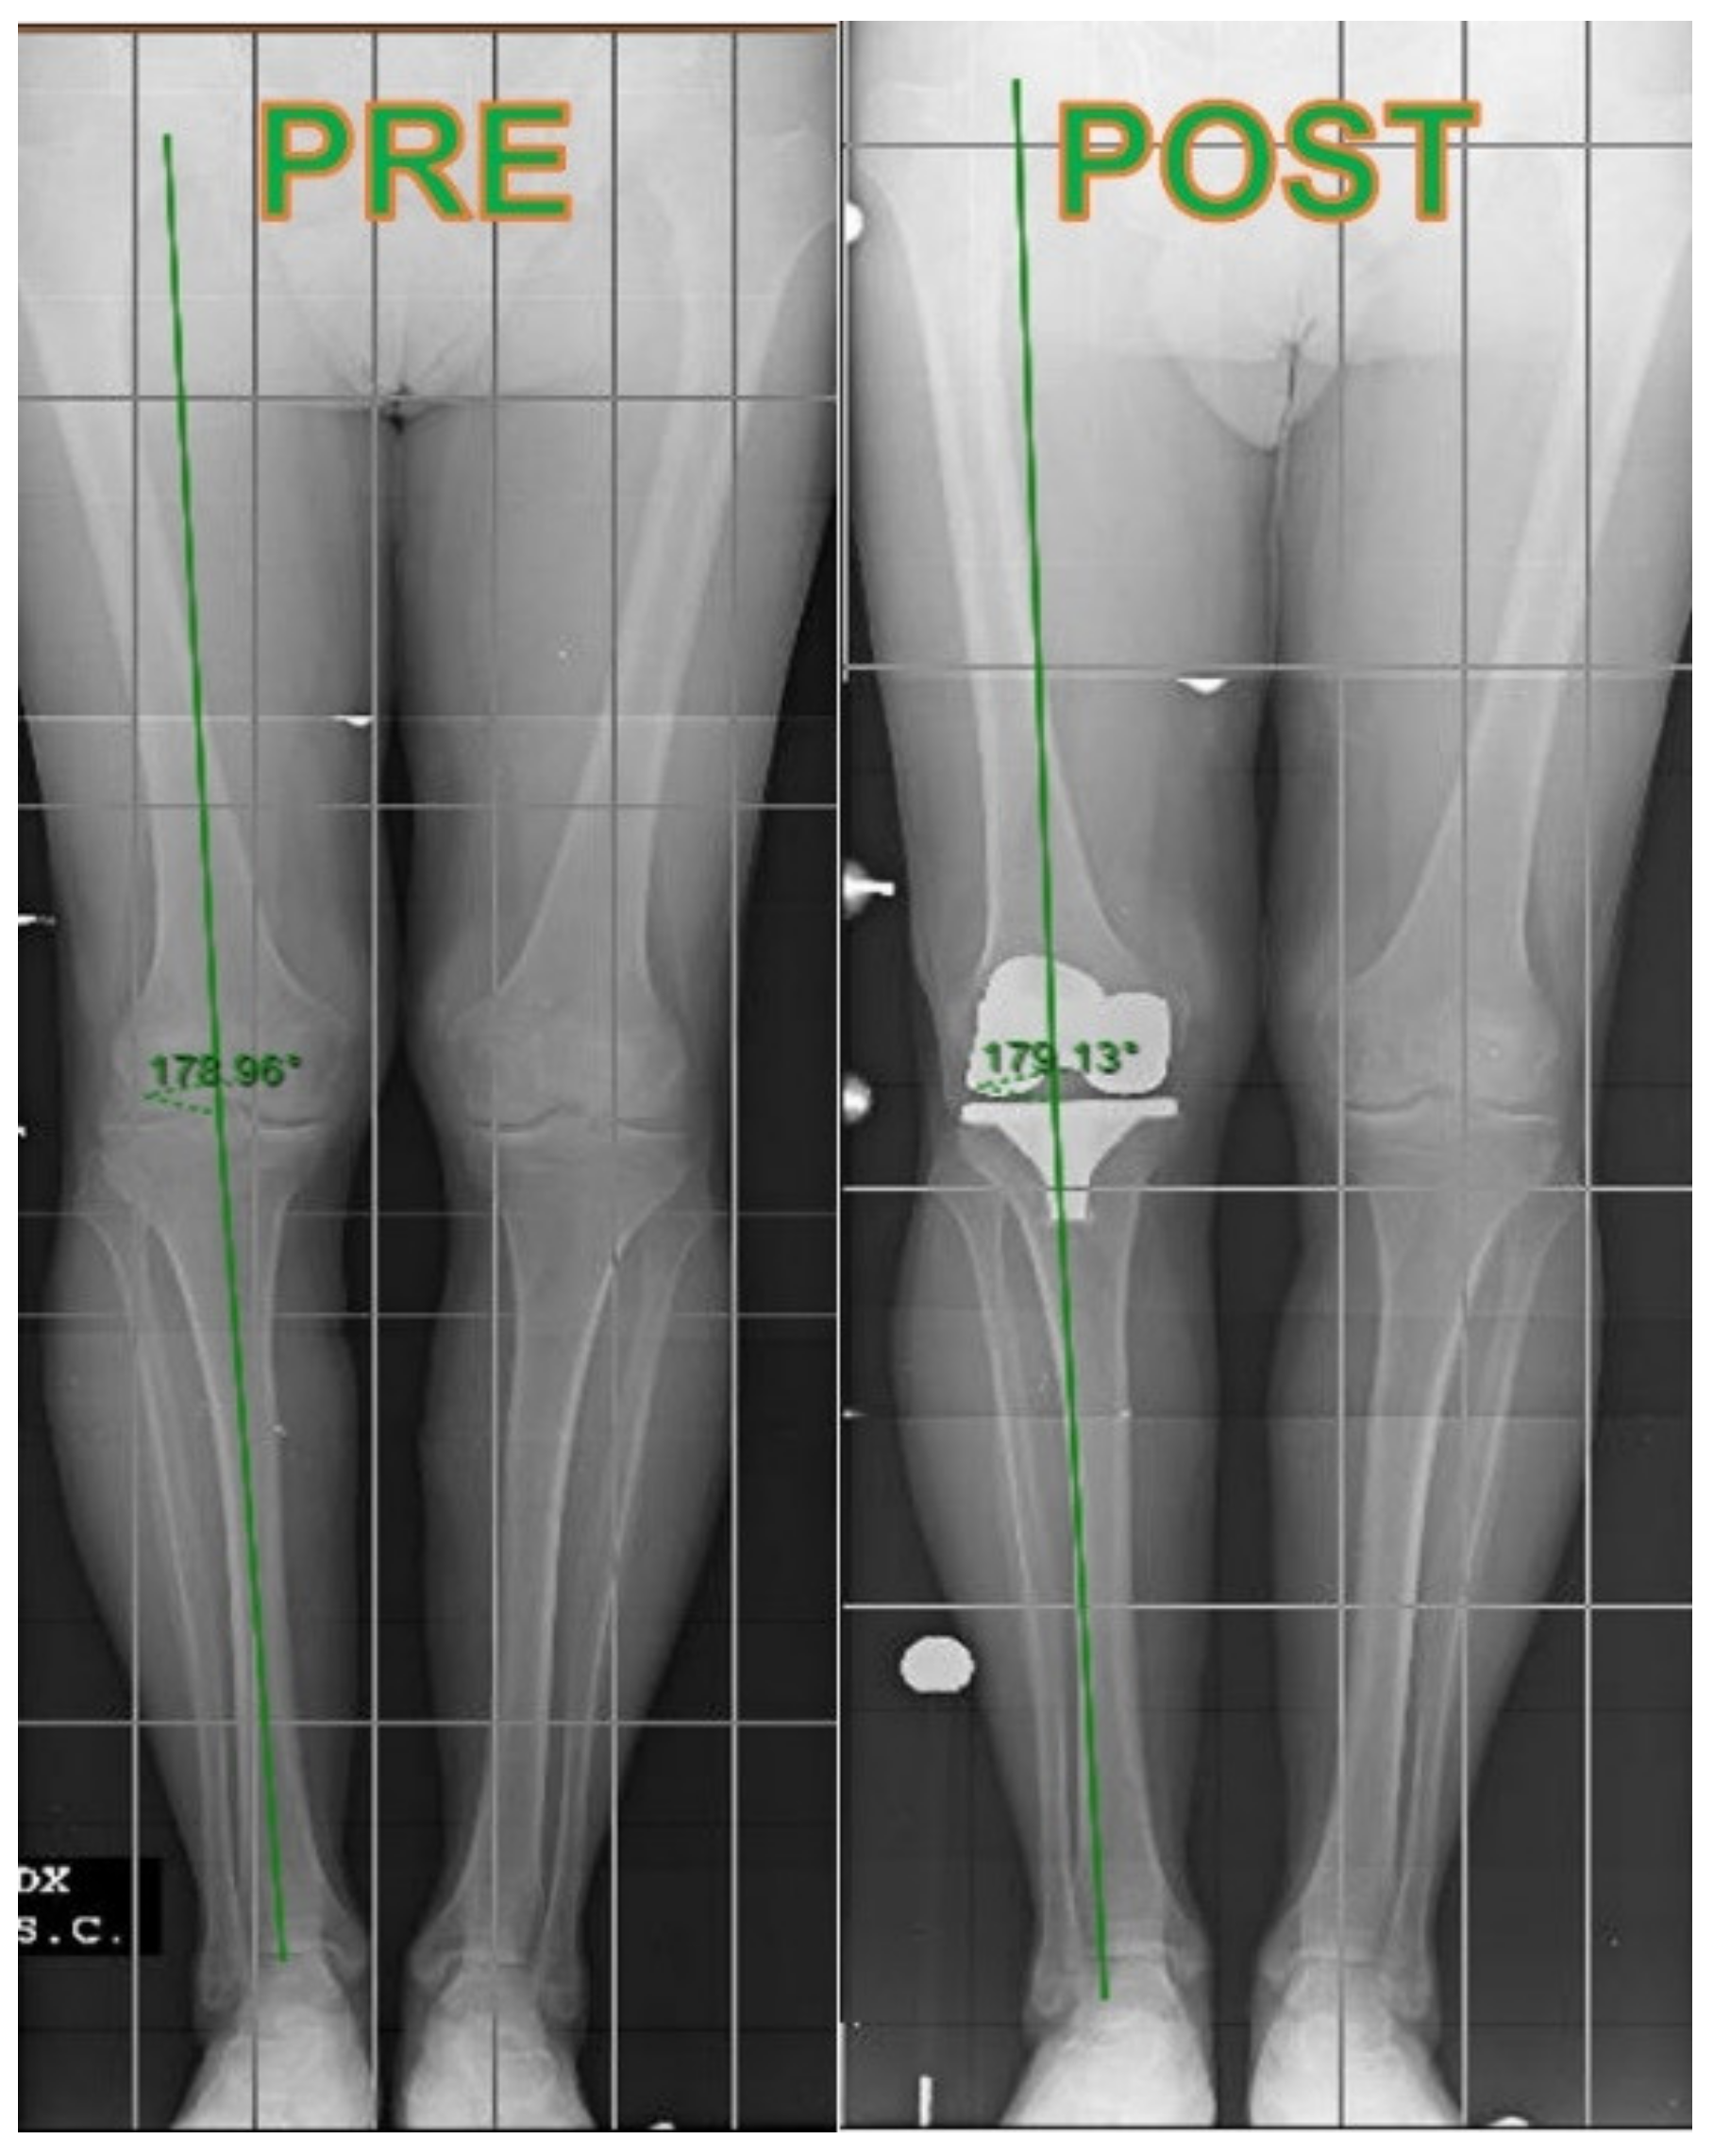

| Radiological Parameters | Varus (+) Valgus (−) PRE | Varus (+) Valgus (−) POST | Femoral Coronal Alignment | Tibial Coronal Alignment | |

|---|---|---|---|---|---|

| CONV | Mean | 4.15 | 0.41 | 93.98 | 89.77 |

| N | 61 | 61 | 61 | 61 | |

| Std. Deviation | 4.52 | 2.22 | 2.01 | 1.09 | |

| Minimum | −7 | −4 | 87 | 88 | |

| Maximum | 10 | 5 | 98 | 93 | |

| NAVI | Mean | 4.28 | 0.44 | 94.11 | 89.97 |

| N | 42 | 42 | 42 | 42 | |

| Std. Deviation | 6.18 | 2.40 | 2.06 | 0.65 | |

| Minimum | −10 | −4 | 89 | 89 | |

| Maximum | 15 | 5 | 98 | 91 | |

| Total | Mean | 4.26 | 0.43 | 94.04 | 89.86 |

| N | 103 | 103 | 103 | 103 | |

| Std. Deviation | 5.29 | 2.29 | 2.02 | 0.92 | |

| Minimum | −10 | −4 | 87 | 88 | |

| Maximum | 15 | 5 | 98 | 93 |